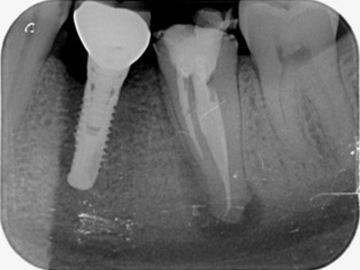

Cas clinique n°1 - Avant / Après